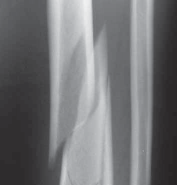

### FIG 3 • Low-energy spiral 43-A type fracture.

24. In contrast to high-energy patterns, rotational injuries ( FIG 3) cause spiral fractures of the distal tibia and fibula originating at the articular level. Intra-articular injury, if present, is typically simple and without comminution or impaction. NATURAL HISTORY